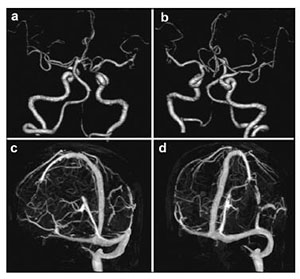

20170712151148  Figure 3 Preoperative computed tomography angiography (CTA; a, b) and computed tomography venography (CTV; c, d) of the brain of the patient.